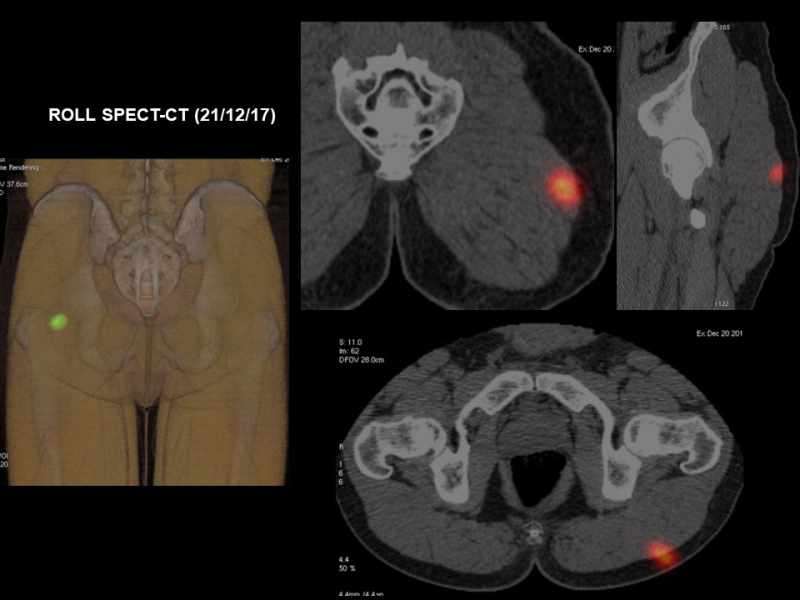

El 21/12/17 se procede a linfadenectomía inguinal izquierda por metástasis ganglionar de melanoma y biopsia/resección de lesión muscular en glúteo izquierdo mediante técnica ROLL guiada por SPECT-CT y ecografía (Fig. 6). El diagnóstico anatomopatológico corresponde a ganglios linfáticos (linfadenectomía inguinal superficial izquierda) con metástasis de melanoma en uno de seis, con extensión extracapsular. El fragmento remitido de músculo estriado (glúteo) se encuentra metastatizado por una neoplasia melánica maligna. No existe afectación de bordes quirúrgicos de resección. El perfil inmunohistoquímico es compatible con metástasis de melanoma. La lesión tumoral es positiva con HMB45 y S100.